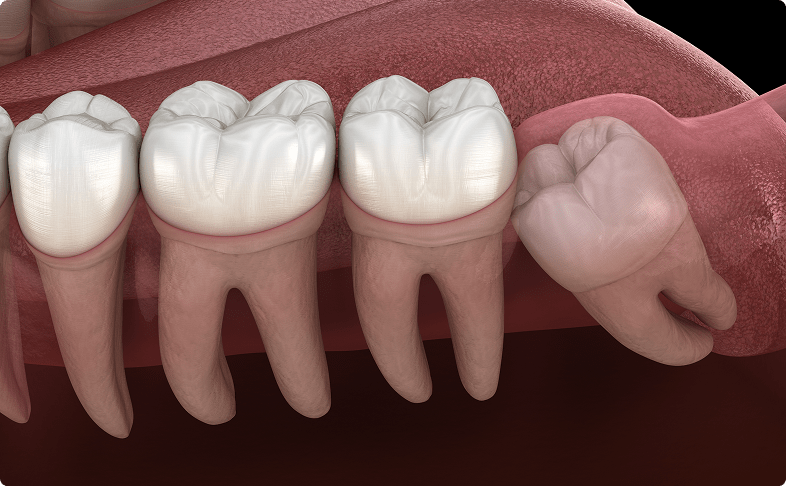

親知らずとは?

親知らずは前から数えて8番目の歯(智歯、親知らず)のことを言います。大きい奥歯(第3大臼歯)では3番目になります。縄文時代など昔の人は普通に生えていたそうですが、現代人の傾向として顎が小さくなってきており、入りきらずに途中で引っかかってしまう状態です。上下左右4本ある人も居れば、もともとない人もいます。悪さをしなければ、絶対抜かないといけないものではありません。

智歯周囲炎

親知らず周囲に汚れがついて歯茎が腫れてしまいます。症状が強く出れば、お口が開けづらくなり、熱が出ることもあります。顔の形が変わるくらい腫れることもよくあります。飲み薬で効きにくい場合は紹介させていただいて点滴処置も必要になることもあります。